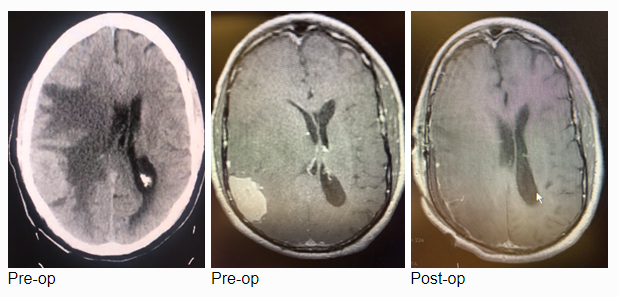

MRI with gadolinium confirmed the likely diagnosis of convexity meningioma, a benign neoplasm of the meninges. Given the location of the tumor, angiography and embolization were deemed unnecessary prior to resection. Stereotactic c-guided craniotomy was performed by Dr. Jonathan Brisman and the tumor was carefully excised from the surrounding brain. A gross total resection was achieved. He was discharged from the hospital to his home, neurologically intact with a slow improvement of his gait. Postoperative MRI showed no evidence of residual tumor.

The patient is an otherwise healthy 80-year-old gentleman who presented with complaints of right frontal headaches and difficulty walking that had progressed over about three weeks. He was neurologically nonfocal. CT scan without contrast showed a large right parietal mass with midline shift and cerebral edema.